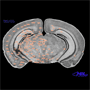

Nissl stain & diagram of

coronal section in

mouse